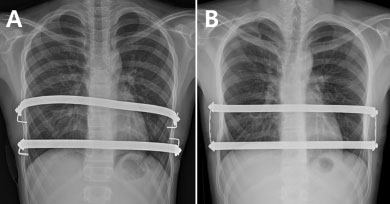

가톨릭대 인천성모병원 정진용 교수팀은 기존 2개의 교정 막대를 개별적으로 고정하는 ‘분리고정 수술법’(사진A)과, 각 교정 막대 양 끝을 작은 금속 막대로 연결해 사각형 형태로 고정하는 ‘사각고정 수술법’(사진B)의 결과를 비교 분석했다.

정 교수팀은 2011년 9월부터 2016년 1월까지 2개의 금속막대를 삽입한 너스수술 환자 86명을 교정 막대의 양쪽 측면을 각각 고정한 A군(44명, 사진A)과 각 교정 막대를 세로형 막대와 연결해 사각형 형태로 고정 시킨 B군(42명, 사진B)으로 나눴다.